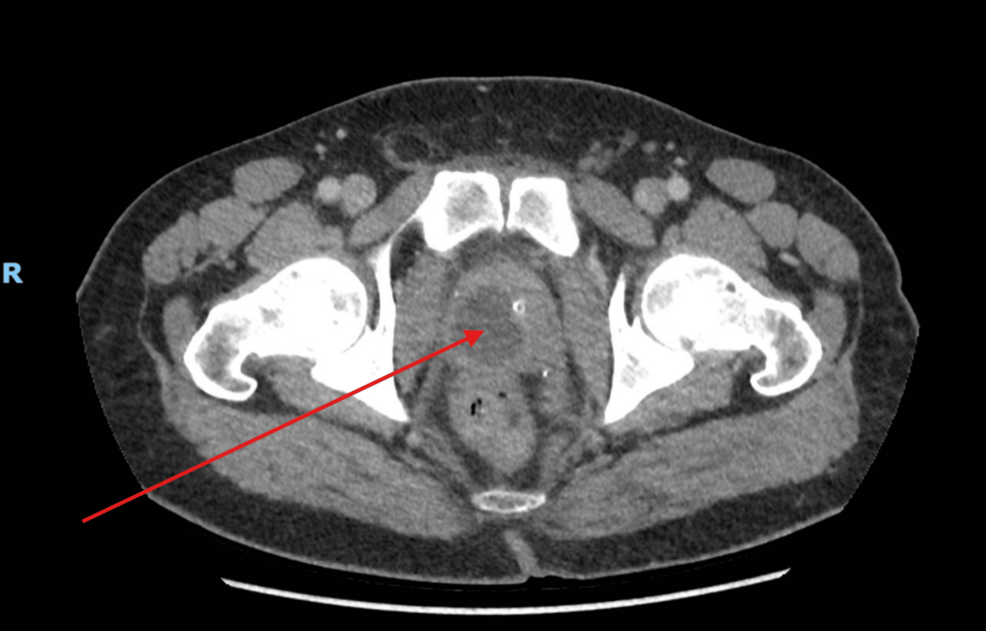

Treating patients at home with IV antibiotics could halve costs to the NHS

Treating patients at home with IV antibiotics, rather than in a clinical setting, could halve costs to the NHS and relieve pressure on hospital beds – according to a University of East Anglia study.